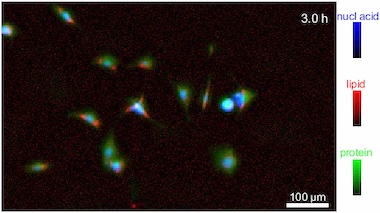

NIST constructed its platform around a hand-built IR laser microscope and applied it to the imaging of the fibroblast cells making up connective tissue in living samples. Over a 12-hour observation period, researchers were able to identify proteins, lipids and nucleic acids during stages of the cell cycle such as cell division, doing so faster than current alternative techniques according to the project.

The SAC-IR method also successfully measured the absolute mass of proteins in a cell, in addition to nucleic acids, lipids and carbohydrates. This capability could help establish a foundation for standardizing methods of measuring biomolecules in cells, potentially valuable in biology, medicine and biotechnology.